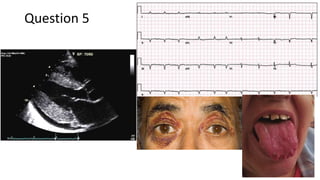

62 years old male, known diabetic and hypertensive for past 20 years presented with acute onset altered

sensorium with altered behaviour and difficulty recognizing relatives. He was admitted and worked up. Routine

evaluation including MRI brain, CSF were normal. Serum ammonia was 305. CT portography done. What is the

diagnosis? What specific intervention can be offered for this indication?

Answer 5

a) Hepatic encephalopathy secondary to portosystemic shunting (Type B HE)

b) Blocking the leino-renal shunt